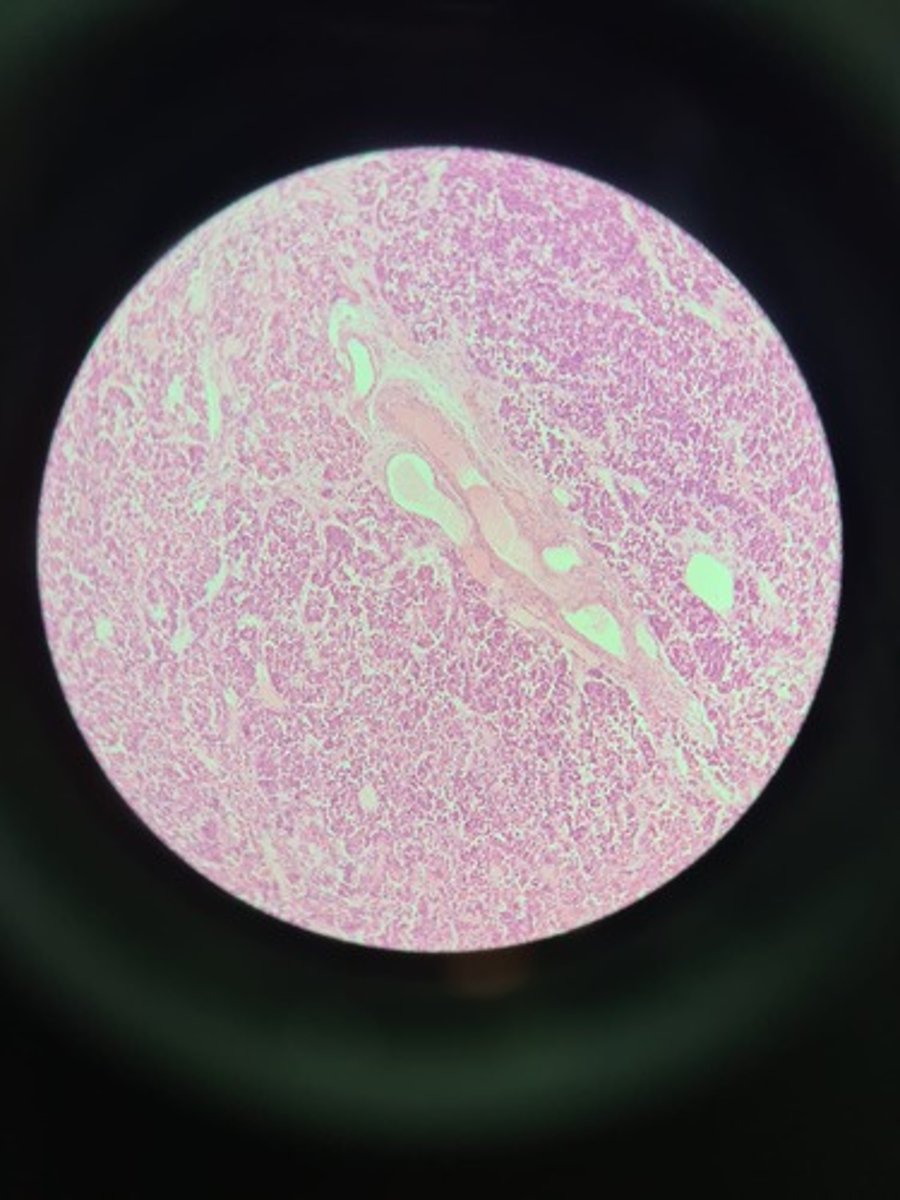

Spleen HE

Spleen HE

Spleen HE